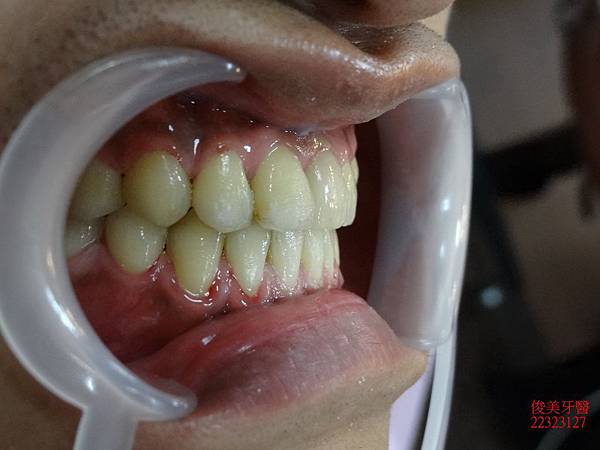

原始狀況~~

咬合狀況。

上排牙明顯被下排牙齒限制住。